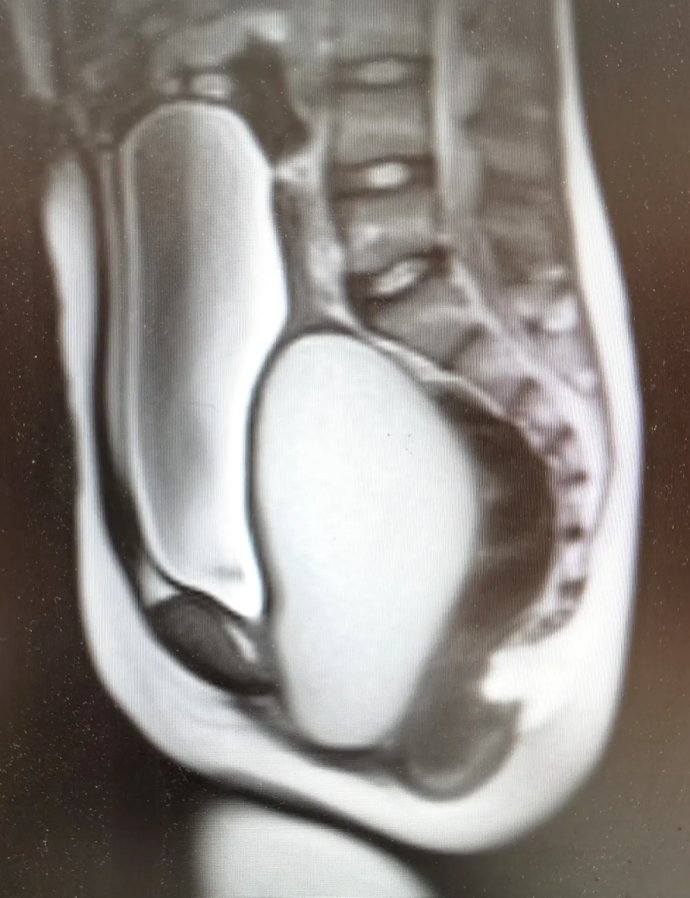

12歲花季少女出現(xiàn)周期性下腹痛,在其父母帶領(lǐng)下先后就診咸陽市兩家醫(yī)院,最終,她們選擇了延安大學(xué)咸陽醫(yī)院婦科。就診當(dāng)日,趙倩蘭主管醫(yī)生詳細(xì)追問病史,患者自訴已間斷性下腹痛3月余,本次腹痛較前明顯加重,腹痛難忍。入院后醫(yī)生立即為其安排了婦科彩超及盆腔磁共振,發(fā)現(xiàn)該患者宮腔、宮頸及陰道上段充滿大量積血,積液壓迫膀胱及直腸,導(dǎo)致排便、排尿障礙。張素寧主任為其查體后發(fā)現(xiàn),該患兒陰道竟無開口,導(dǎo)致經(jīng)血無法排出,閉鎖處無隆起,無青紫,排除處女膜閉鎖,直腸檢查發(fā)現(xiàn)陰道上端有一包塊凸向直腸,包塊下緣距離肛門口約4-5cm,結(jié)合查體及相關(guān)輔助檢查,考慮該患者為陰道閉鎖,值得慶幸的是該患者其他系統(tǒng)暫未發(fā)現(xiàn)畸形。

盆腔磁共振圖像